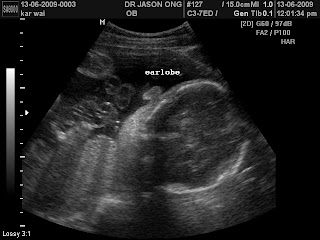

* The THING!!!!...Enjoy you weekend people.....hopefully there will be a suprise announcement in the coming post.......